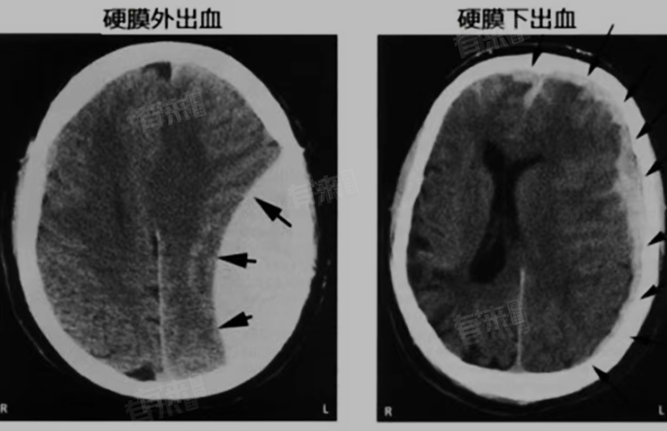

- 硬膜外血肿在CT上通常表现为颅骨内板下方纺锤形或梭形的高密度影,边缘清晰,形态较为规则。有时也可能呈现为双凸形,类似于凸透镜样的影像。

- 硬膜下血肿的形态多样,最常见的是新月形或半月形,其边界不如硬膜外血肿清晰,往往显得较为模糊。这是由于血液在蛛网膜下腔的广泛分布所致。

- 硬膜外血肿在CT上通常表现为高密度影,特别是在急性期,由于血液密度较高,CT上的影像会显得更为明亮。随着病情的发展,血肿的密度可能会逐渐降低。

- 硬膜下血肿的密度表现会根据其所处的时期而有所不同。急性硬膜下血肿在CT上表现为颅骨内板下方新月形的高密度影;慢性硬膜下血肿则可能表现为等密度或低密度的新月形影,与脑组织的密度相近。